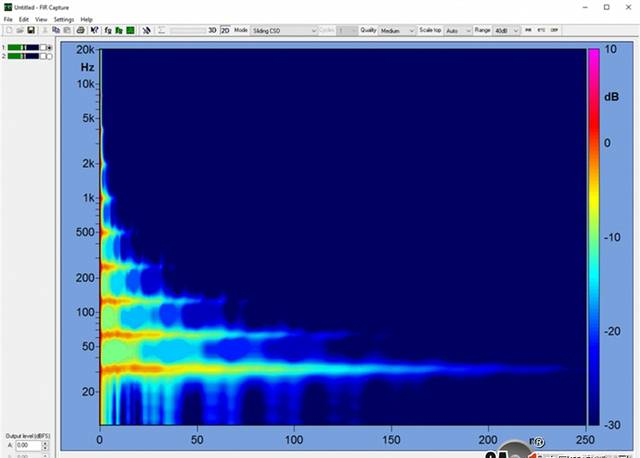

一、读懂听力检查报告孩子听力检查报告,林林总总不过是那么几样:声阻抗、听觉脑干电位ABR、多频稳态ASSR、(颞骨)CT影响检查(显示中、内耳及内听道情况)等等。医院一般...